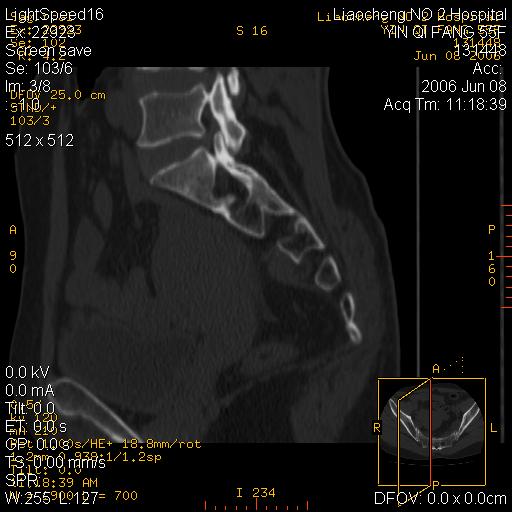

女,55岁,十余年前骶尾骨摔伤,x线平片诊断骶骨裂纹骨折,现在骶尾部又疼痛2月,x线怀疑骶骨左下部骨质破坏。大家看看,是不是先天变异。正常人不是只有4个骶孔吗?怎么此病例有5个?

两侧骶髂关节炎,确实做得很漂亮

众口一词啊,图象确实漂亮,羡煞人也!右侧骶髂关节间隙变窄,相对缘增生硬化,髂骨侧增生明显。左侧轻微类似改变,考虑双侧骶髂关节炎。余未见异常。

图像确实漂亮,骶髂关节及骶尾椎均未见异常。

图象很漂亮,骶骨未见异常,感觉右侧骶髂关节髂骨面密度增高,不知是否异常?